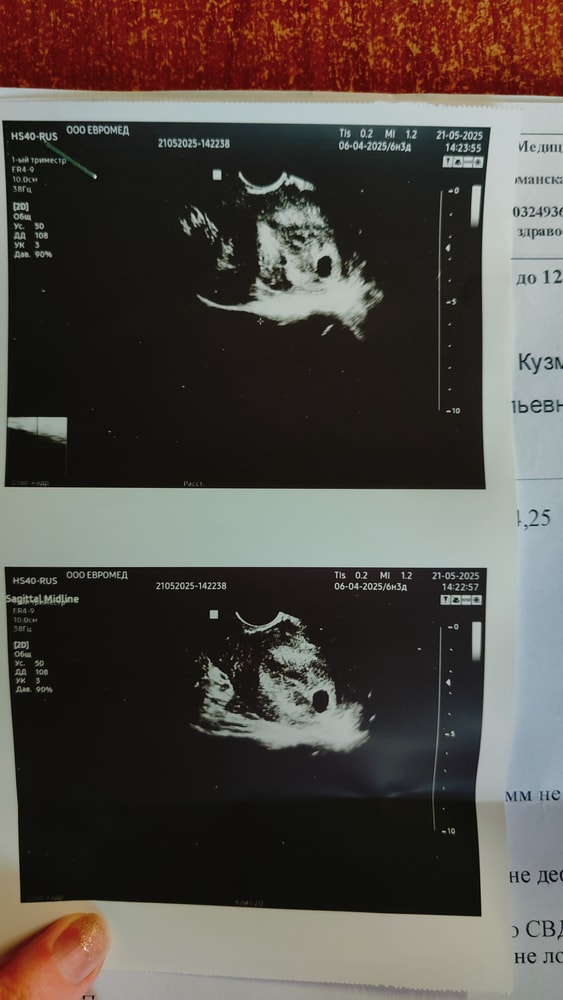

28дпп- УЗИ ПЯ-10мм, но эмбриончика не увидели, сказали повторить через 2 недели и Контролировать хгч ( При прошлой беременности тоже увидели ближе к концу 8 или 9 акуш.недели,это точно помню)

Слишком маленький пя на 28 дпп и нет желточного мешочка. Сделайте уже через 5 дней, уже все точно станет ясно

РЕКА

Не переживайте, хотя сама тоже страху натерпелась. 28дпп это примерно 5 недель? У меня на 28дц (14дпо примерно) шикарный хгч 1221. На 29 дц узи плодное яйцо 3мм.-это 4 и1 нед по месячным. Делаю узи в 5,1 нед. плодное яйцо 10,03мм, нет эмбриона, нет желточного. Прошло 4 нервных дня. Узи в 5.5 эмбрион 3,8 послушали сердечко. ПЯ 26 мм. Очень переживала, что у девочек при хгч сильно меньше, уже все нашли сильно раньше. Мы все разные.

Параметры хгч, размеры плодного все очень индивидуально.